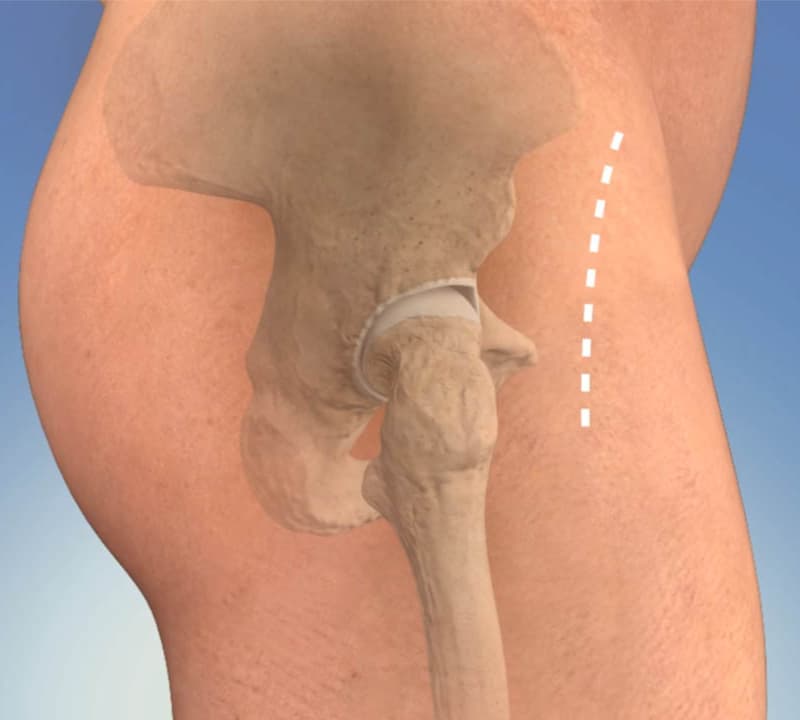

When deciding to undergo hip replacement surgery, it is important to know how the surgery is performed as it will impact your recovery from surgery. Hip replacement has traditionally been completed through a posterior approach requiring the cutting of muscles and tendons which can slow down recovery.

Dr. Applonie offers hip replacement with a muscle sparing approach called the anterior approach. The implant positioning and leg lengths are confirmed directly during surgery. You will begin placing full weight on the hip replacement directly after surgery with the goal to complete physical therapy goals of ambulation and even stairs on the first day of surgery.

• Less muscle trauma as it doesn’t require cutting any muscles or tendons